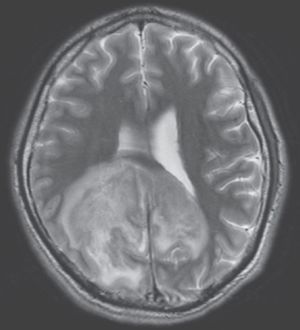

A 31-year-old man from El Salvador, recently diagnosed with HIV/AIDS, presented to the emergency department with headache, confusion, gait instability, and fever. Brain MRI showed a large mass in the right parietal and occipital lobes. Brain aspirate identified Trypanosoma cruzi. What vector is likely responsible for transmission of this protozoa to this patient? a) Anopheles mosquito b) Triatomine bug c) Ixodes tick d) Phlebotomine sand fly e) Tsetse fly source: nejm.org